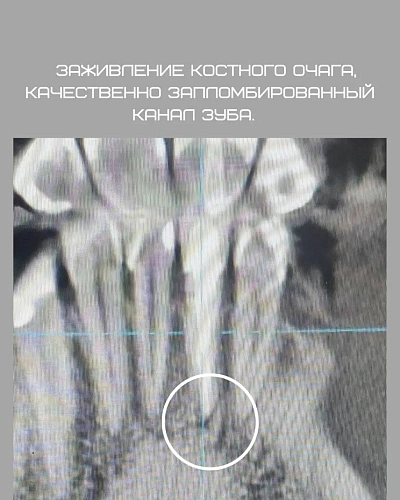

Рассмотрим клинический случай: пациент обратился с бессимптомным течением хронического периодонтита. Мы решили провести ревизию корневых каналов под микроскопом для устранения патогенной микрофлоры. Спустя три месяца после лечения мы наблюдаем положительные результаты — источник костного разрежения значительно уменьшился, а инфекция была успешно устранена.

Лечение бессимптомного хронического периодонтита под микроскопом демонстрирует свою эффективность: положительная динамика наблюдается уже через 3 месяца.